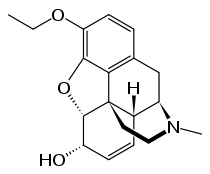

Structures

| Morphides | ||||

|---|---|---|---|---|

Codeine Codeine |

Morphine Morphine |

Oripavine Oripavine |

Pseudomorphine Pseudomorphine |

Thebaine Thebaine |